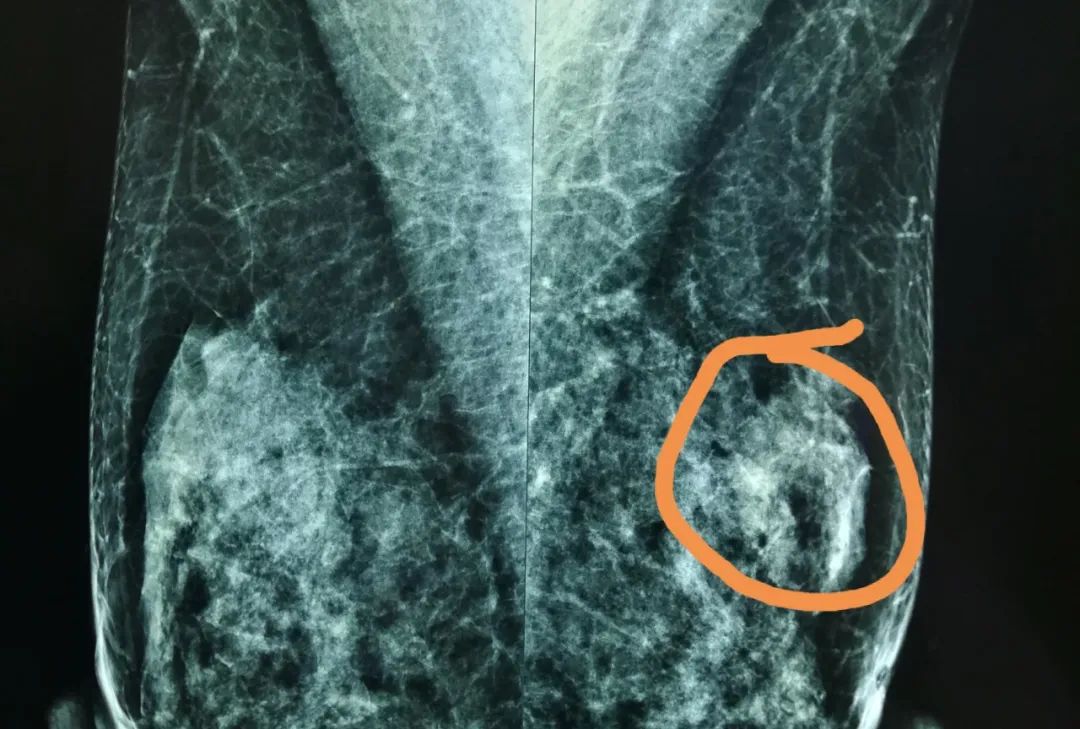

谢主任介绍,患者在接受钼靶、超声、磁共振等检查乳房时,医生一般会根据Bi-rads分类系统,在检查报告上标明0-6的分类,这对于判断乳腺癌早晚期和制定治疗方案有一定参考意义:

0类代表需要增加其他影像检查;1类代表正常;2类代表肯定良性;

3类代表良性可能性大,恶性可能在2%以下,患者要半年一次定期检查。

4类代表可疑异常,并继续分成4A(恶性可能在2%-10%)、4B(恶性可能在10%-50%)、4C(恶性可能在50%以上),应考虑活检。

5类代表高度怀疑恶性,有典型乳腺癌的影像学特征,恶性可能性大于95%。6类则代表已行活检证实为恶性,临床应采取适当措施。